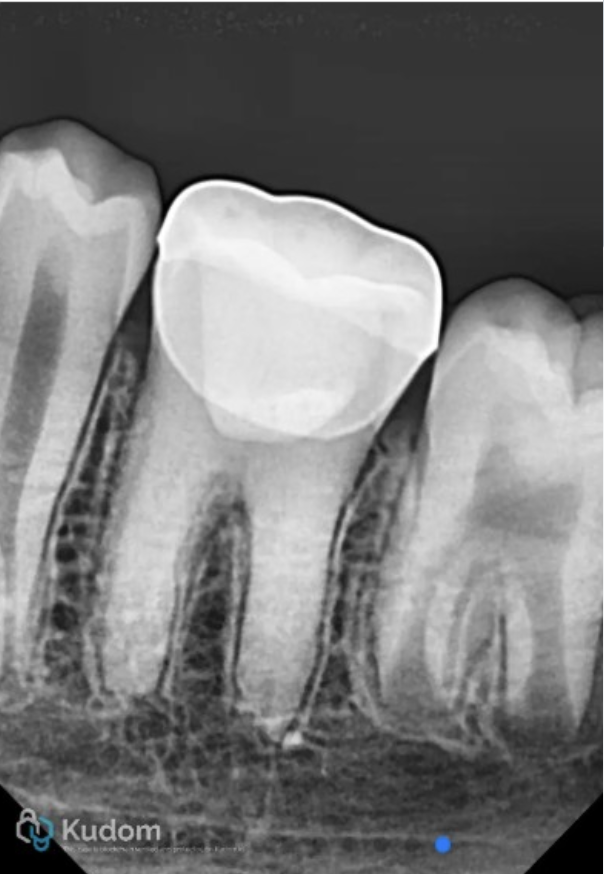

Fig. 1

An 8-year-old female patient reported to the clinic with complaint of pain in left mandibular molar tooth. Clinical and radiographic examinations revealed a carious nonvital 36 with immature root apex. The stage of root maturity corresponded with Demirjian’s stage G (wide open apical foramen and nearly completed root length).

The X-ray shows deep carious lesion in tooth 36. The root length is nearly complete with wide open apical foramina and indistinct apical lamina dura around both mesial and distal roots.